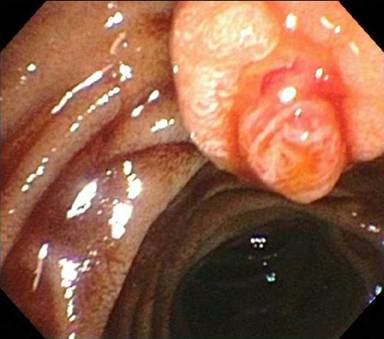

A 47-year-old African American male was admitted to the hospital for left chest wall abscess and diabetic ketoacidosis. Past medical history included diabetes mellitus type 1, essential hypertension, paroxysmal atrial fibrillation, ischemic stroke with minimal residual right sided paralysis, and chronic kidney disease. During the appropriate treatment of his admitting complaints, and management of his comorbidities, which included anticoagulation for the history of paroxysmal atrial fibrillation with CHADS score of 4, his hemoglobin dropped precipitously from 10 g/dL to 8.5 g/dL, then stabilized, then again dropped to 6.7 g/dL. Evaluation included esophagogastroduodenoscopy, which revealed fresh blood from second portion of duodenum, emanating from the ampulla (Figure 1). Contrast-enhanced MRI (Figure 2) showed a solid lesion within the pancreatic tail, measuring 1.8x1.5 cm, hyperenhancing and consistent with a pancreatic neuroendocrine tumor (PNET); there was no liver lesion identified. Endoscopic ultrasound (EUS) was concordant regarding size, shape, and location of the pancreatic lesion, and furthermore showed no stones, masses, or dilatation of the common bile duct (Figure 3). Biopsy of the pancreatic tumor was not performed due to concern for bleeding.

Figure 1. View at EGD, with gross blood emanating from major papilla. |